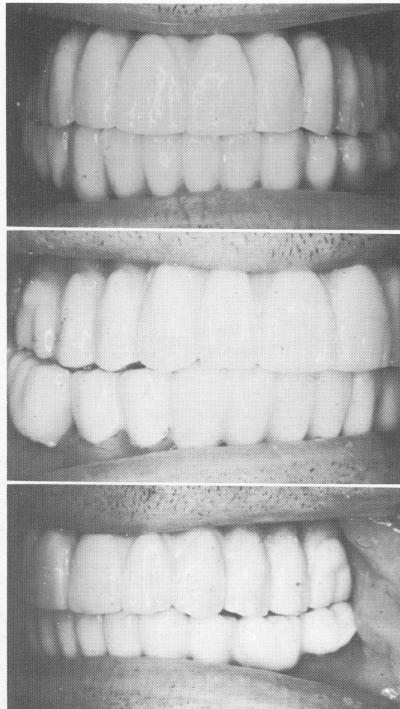

By the time the bridge was ready for final insertion, the tissues around the posts were completely healed and closely adapted (Fig. 11-155). The full arch fixed denture, made of acrylic-over-gold, was cemented over the metal posts with hard cement (Fig. 11-156). The occlusion was then carefully spot-ground for any other prematurities caused by the addition of the cement (Fig. 11-157).

Fig. 11-156. The final prosthesis in place.

Fig. 11-157. The final prosthesis was articulated.

2 Full maxillary arch fixed denture, made of acrylic over gold in place

3 Final maxillary prosthesis articulated